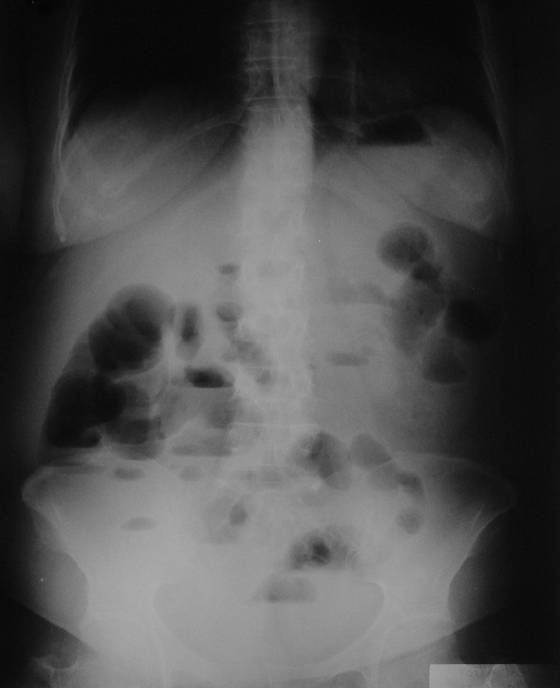

Konvansiyonel Radyoloji

• Direkt grafiler genellikle akut karın sendromu varlığında ya da akut tıkanıklıkta.

• Kontrastlı grafilerde oral yolla verilen baryumun kontrast ajan olarak kullanılması ile ince barsak pasaj grafileri çekilir.